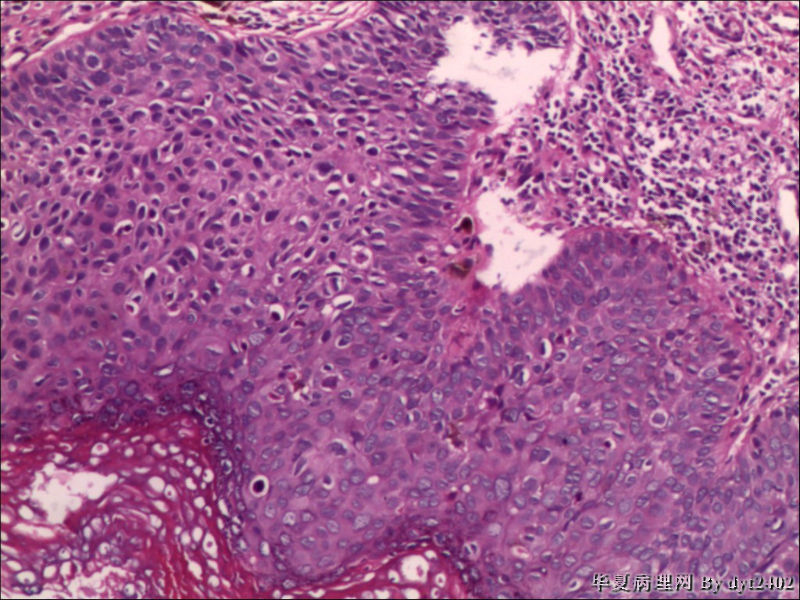

这样的外阴病变 发个原位癌是否合适?

• 这样的外阴病变 发个原位癌是否合适?图2

图2

原位癌够了,不排除其他地方有浸润。

似乎有浸润了

VIN III,做个银染或者标个免疫组化看一下基底膜是否完整。

看上去好像还完整 只是经常看见图5 那样结构的就觉得可能还有更重病变

VIN III